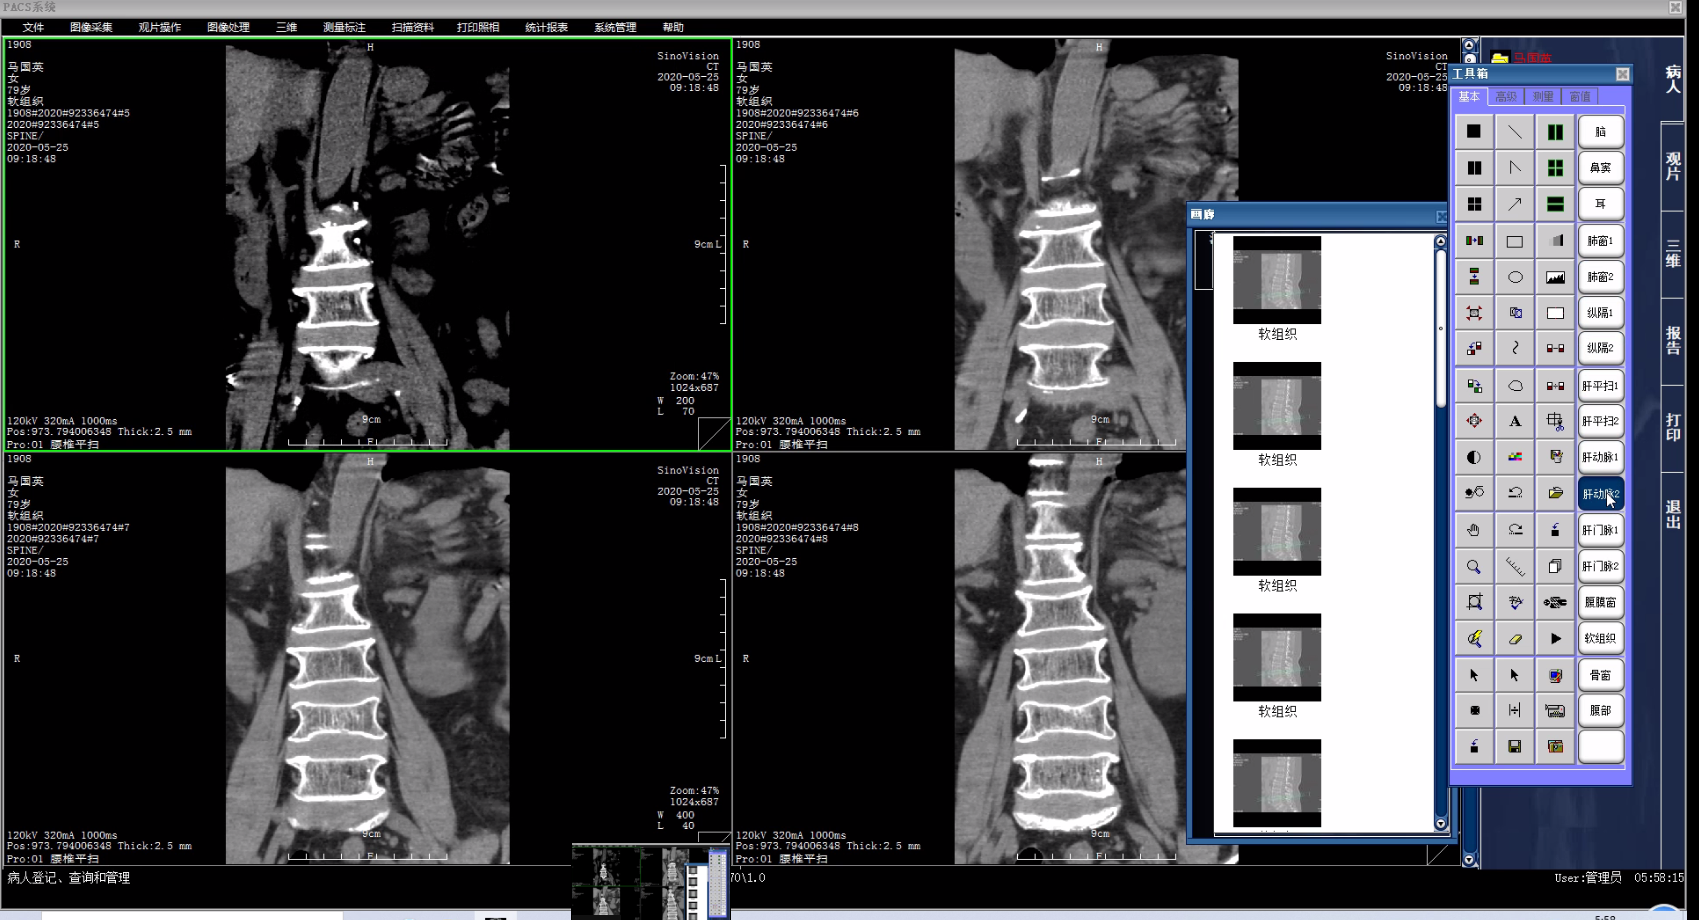

二、PACS影像系统源码,带三维重建和还原的PACS系统源码

三甲医院医学影像PACS系统源码,集成三维影像后处理功能,包括三维多平面重建、三维容积重建、三维表面重建、三维虚拟内窥镜、最大/小密度投影、心脏动脉钙化分析等功能。系统功能强大,代码完整。

1、C/S架构的PACS系统可实现检查预约、病人信息登记、计算机阅片、电子报告书写、胶片打印、数据备份等一系列满足影像科室日常工作的功能。

2、相关技术:C语言+数据库 : MSSQL+开发工具 : VC